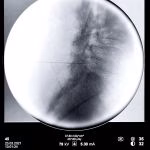

- Rizotomia percutânea lombar

- Implante de neuroestimulador medular